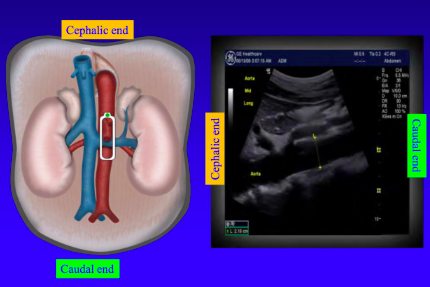

When the ultrasound probe is sagittal (longitudinal) the left of the image is _________

cephalic (towards head)

When the ultrasound probe is sagittal(longitudinal) the right of the picture is _________

caudal (towards feet)

The probe marker is towards the patient's \__________ when the probe orientation is sagittal

head